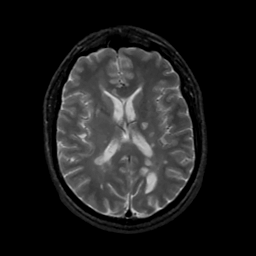

MR Study #15, June 9, 1991 -- Slice #29

[Home][Help][Clinical][Tour 1][Tour 2] Slice 29